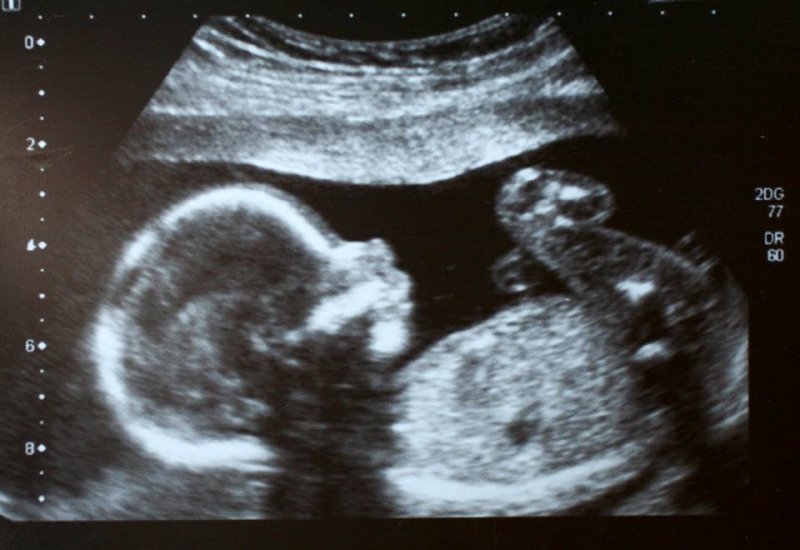

ClujToday.ro: Incep cele 40 de zile pentru viata, miscarea anti-avort care uneste toate confesiunile

A şaptea ediţie a campaniei “40 de zile pentru viaţă” se va desfăşura la Cluj-Napoca în perioada 26 septembrie –…